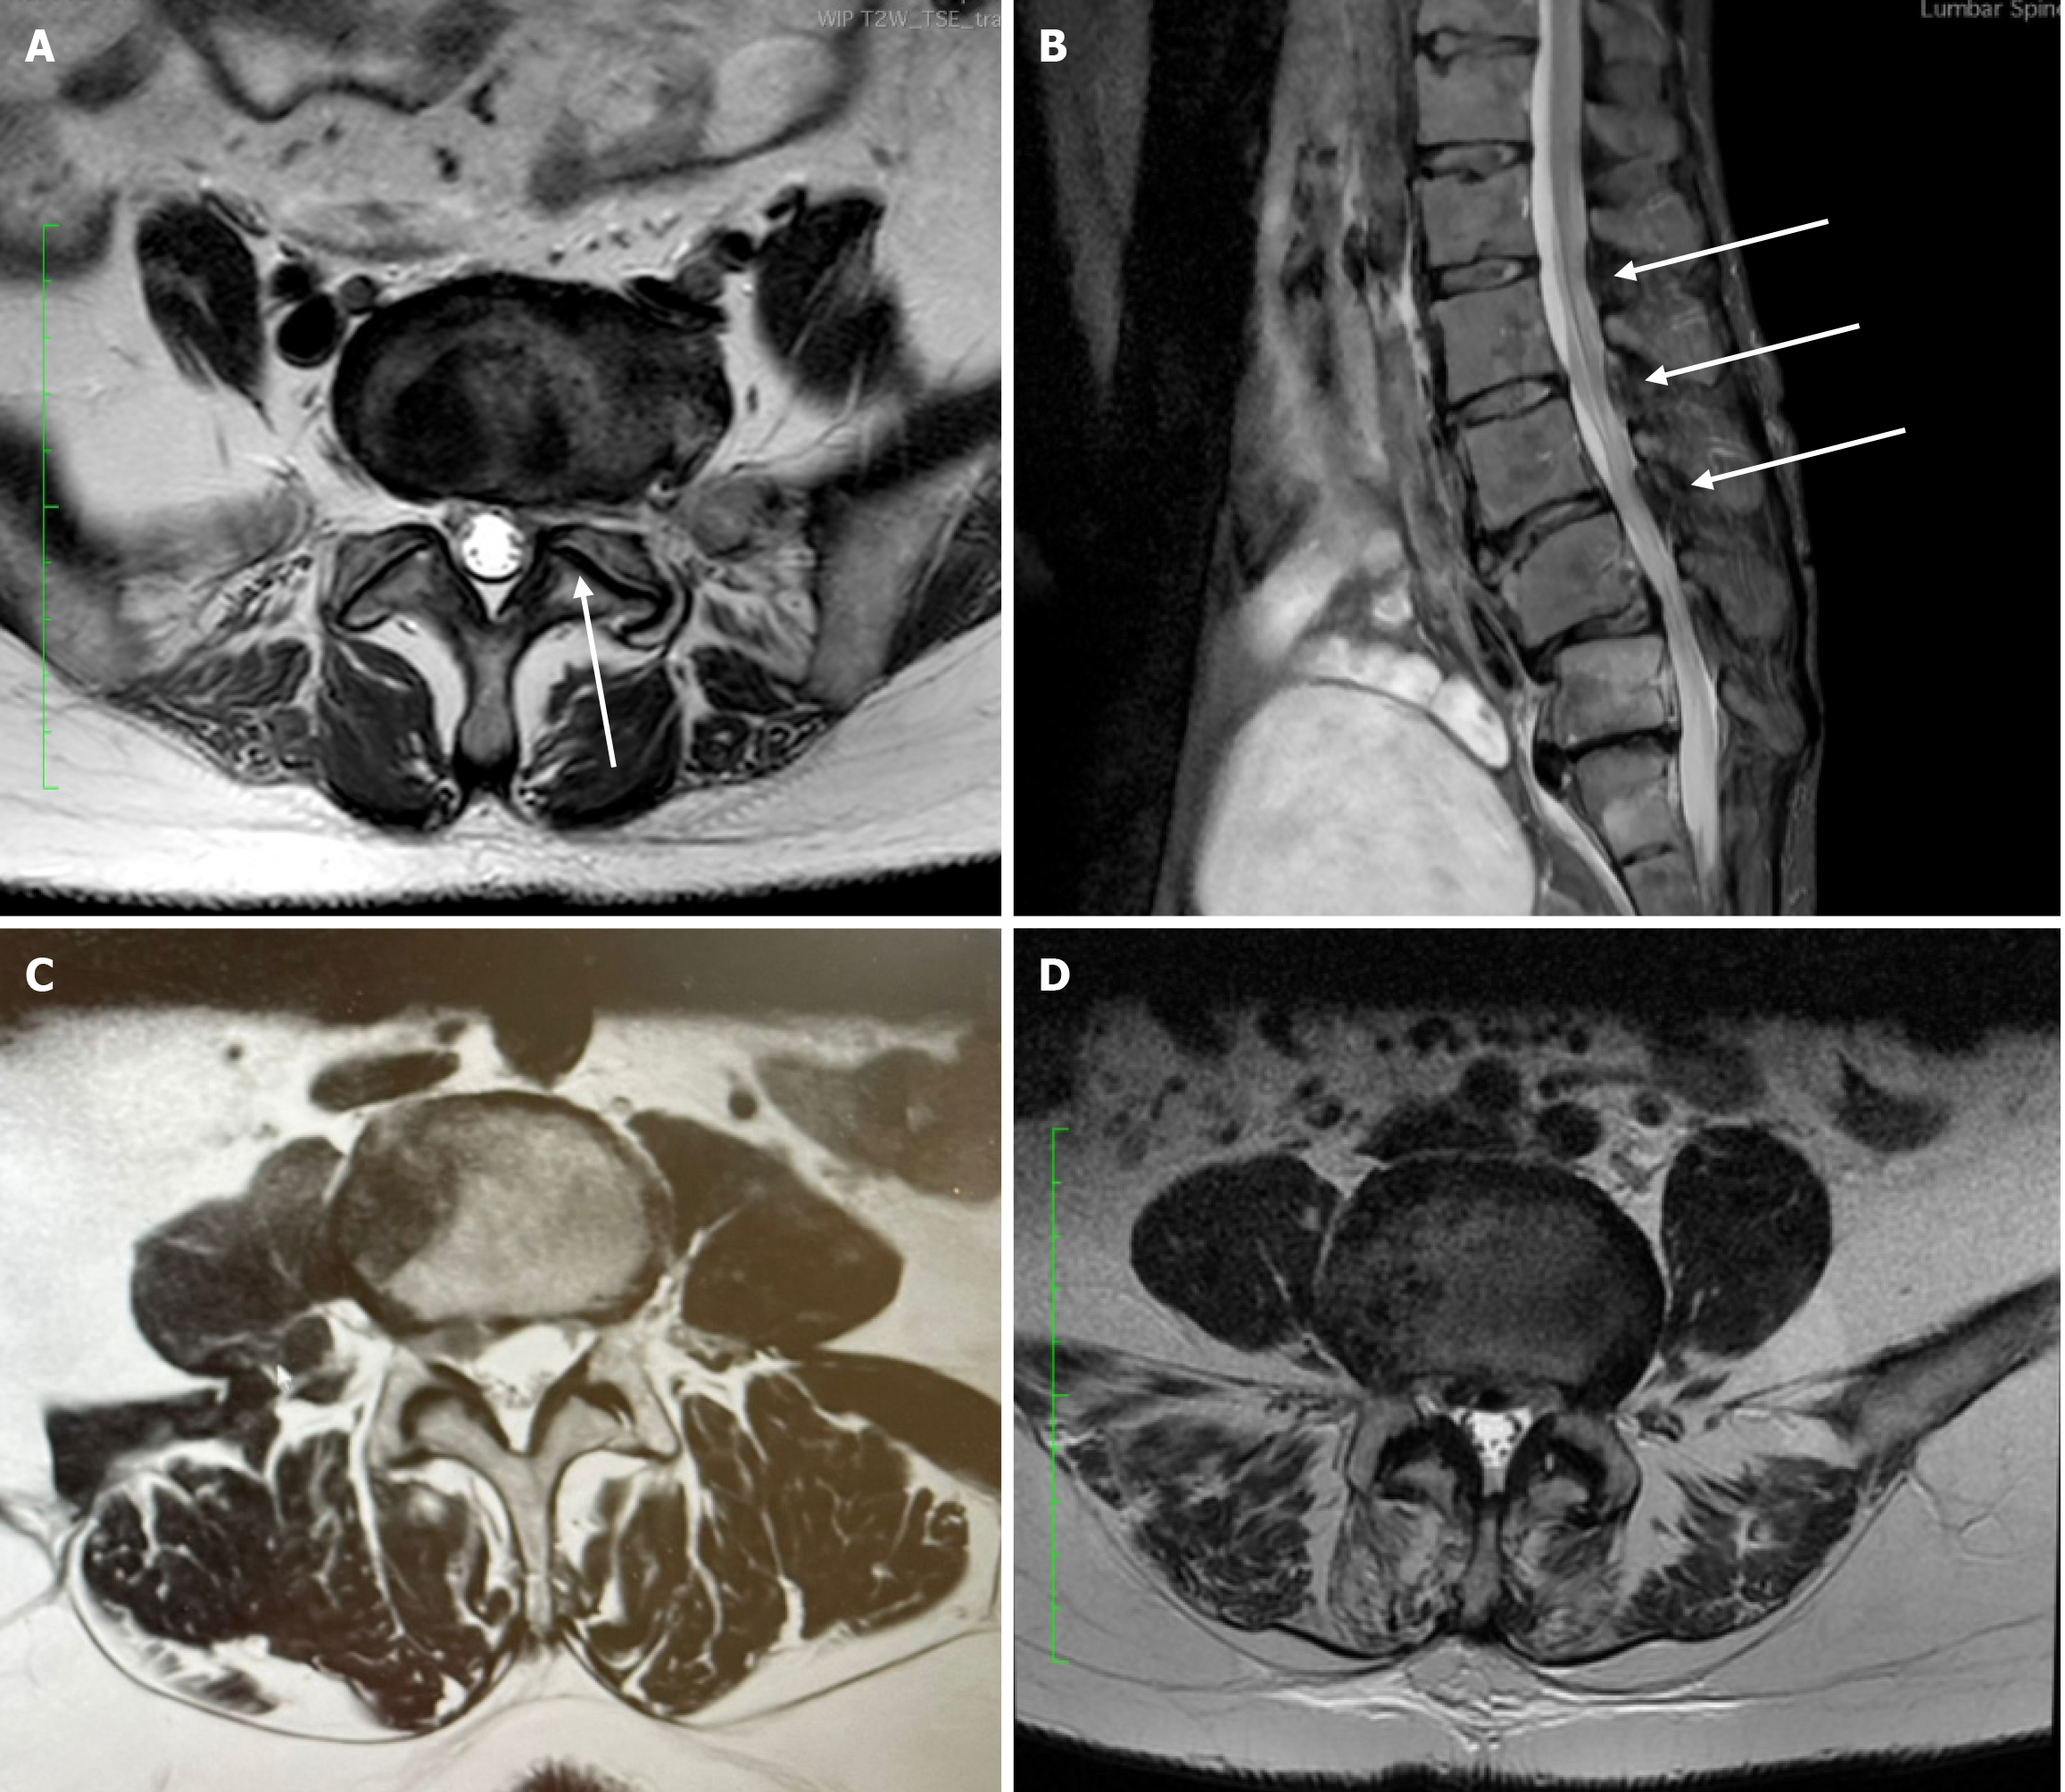

This procedure also follows the standard midline posterior approach but is most commonly followed by pedicle screw instrumentation and grafting to achieve arthrodesis of the affected segments[39]. This type of fusion can be performed with or without interbody support, depending on the patient’s anatomy, specific pathology or surgeons’ preferences[38,39]. Whenever pedicle screws are used, they are inserted bilaterally into the vertebral pedicles under fluoroscopic guidance. These screws are then connected using longitudinal rods to restore the original alignment and provide stability. Intraoperative navigation or neuromonitoring may be used to reduce the risk of neural injury, especially in complex cases. Figure 3 shows postoperative lumbar fusion with pedicle screw fixation without grafts or implants.

Figure 3

Figure 3 Postoperative lumbar spinal fusion with pedicle screw instrumentation. Lateral (left) and anteroposterior (right) plain radiographs demonstrate solid fixation at the instrumented level with bilateral pedicle screws and connecting rods.